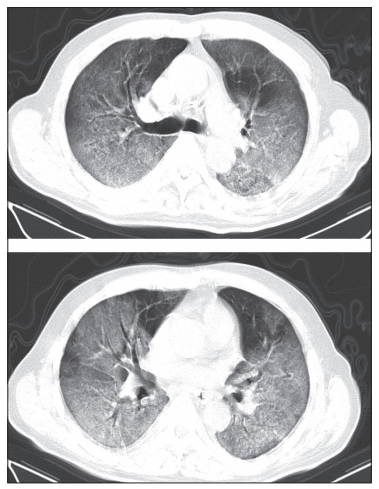

新型冠状病毒感染的肺炎不同时期ct影像学表现

全解析!6例新冠肺炎确诊者不同时期ct影像学表现